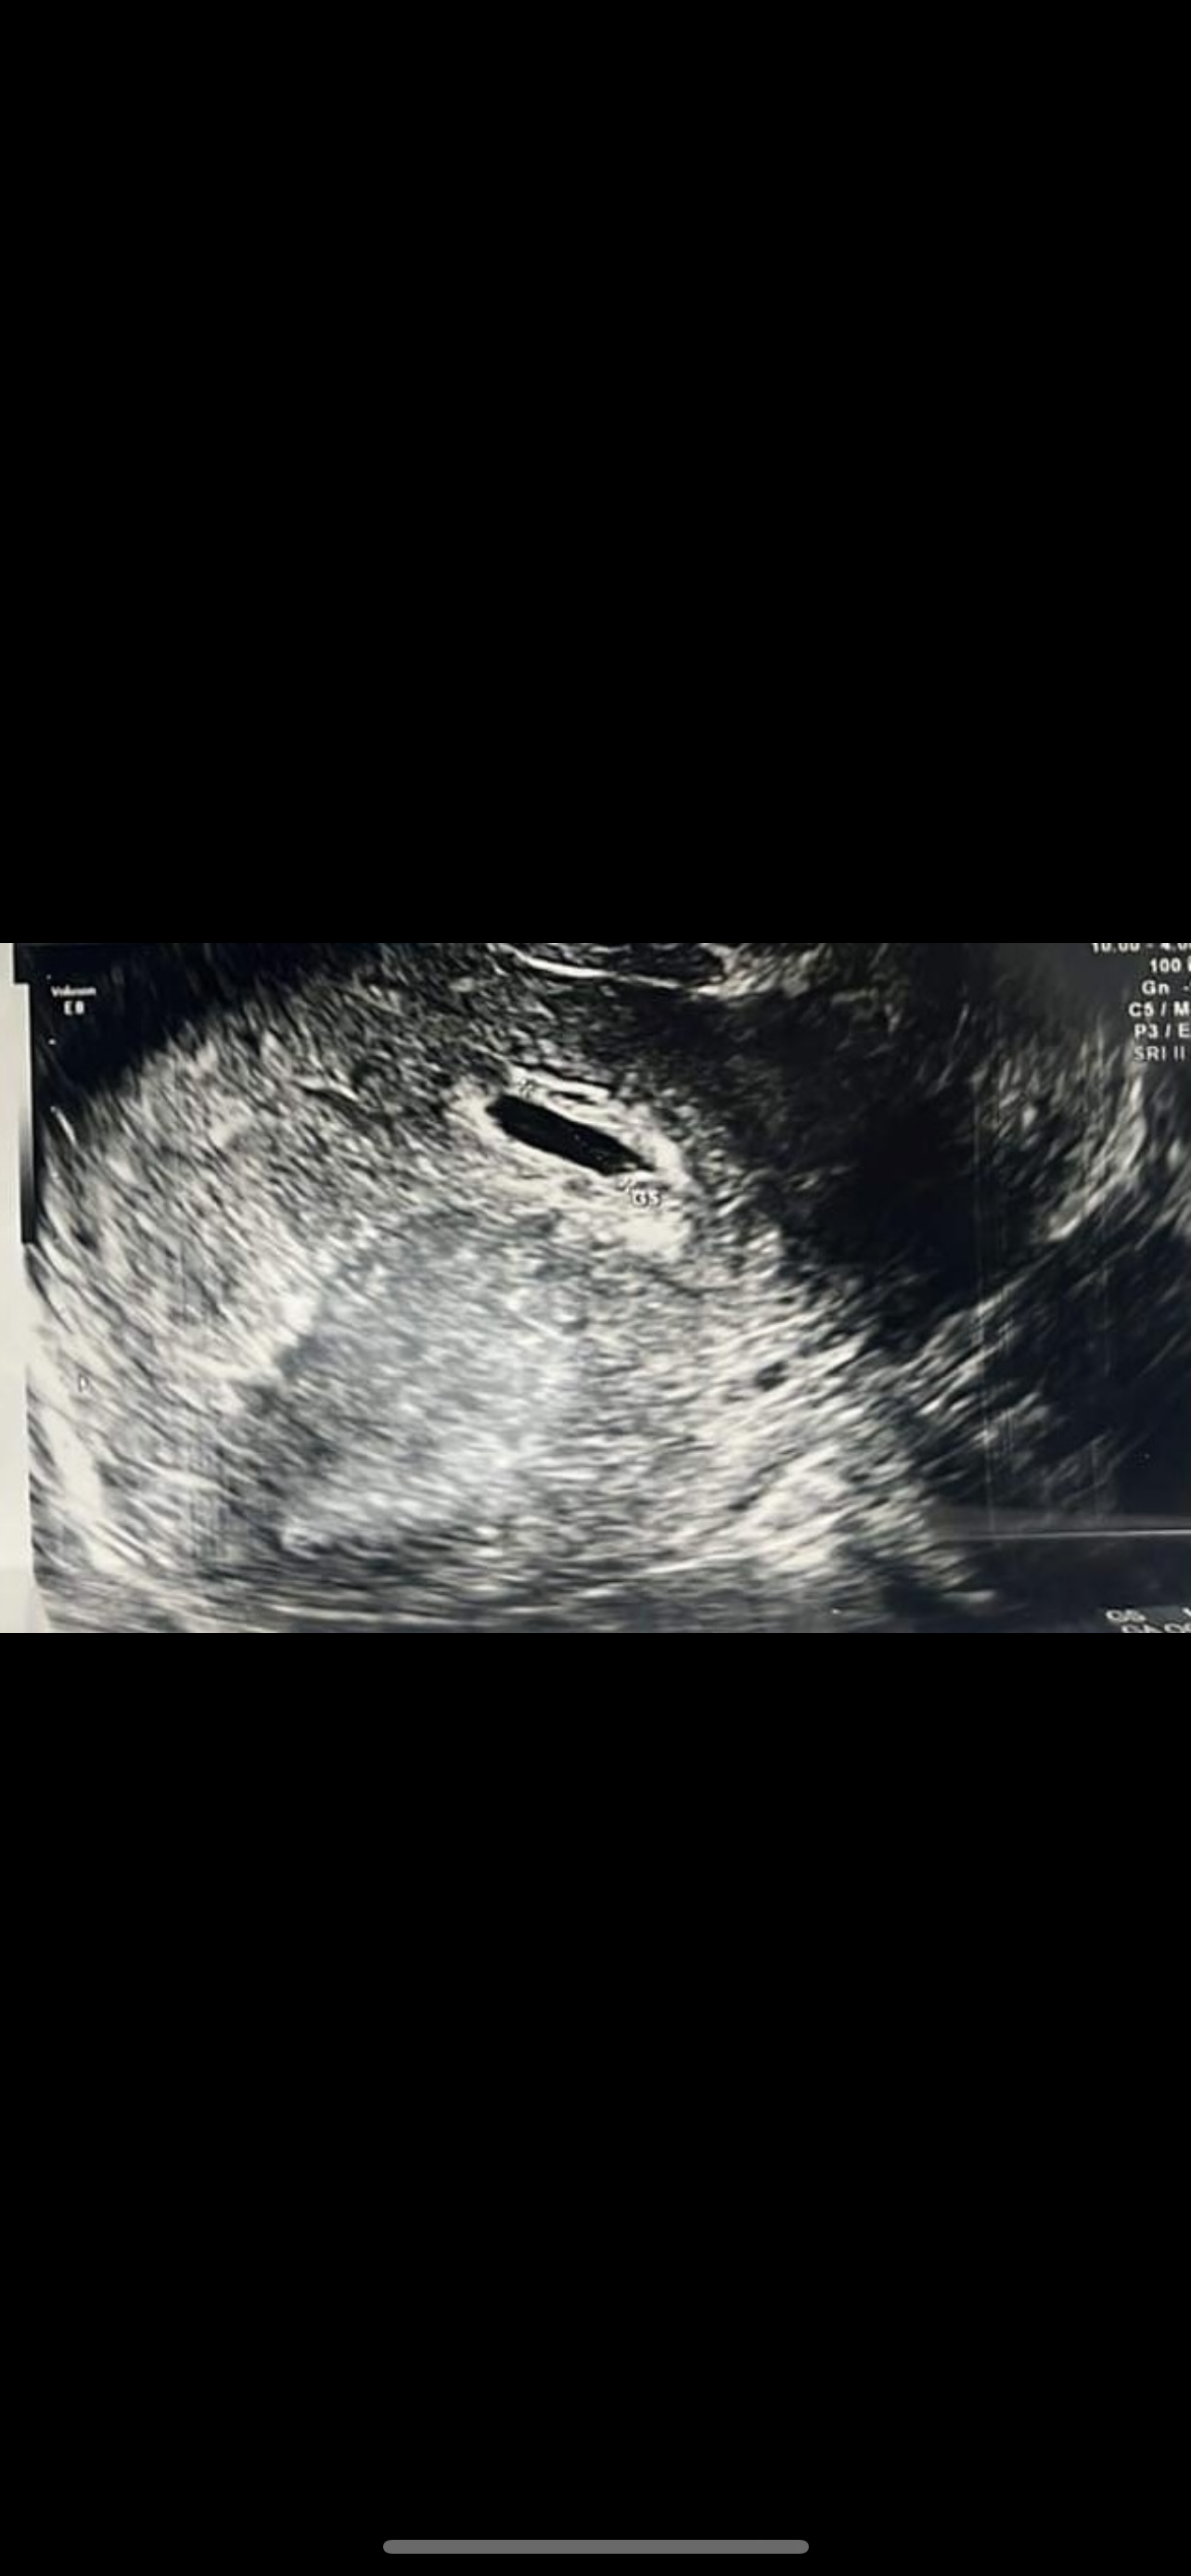

Badanie usg, za mały pęcherzyk

W dniu dzisiejszym byłam na potwierdzeniu ciąży Pan doktor powiedział ze jest zle. Pęcherzyk jest za mały i ma zły kształt. Wymiar to 11mm.

Bardzo was proszę o pomoc, co o tym myślicie? Była któraś z was w takiej sytuacji? Czy na tym zdj jest pęcherzyk żółtkowy? Nie wiem co mam o tym myśleć. Proszę o odpowiedz.